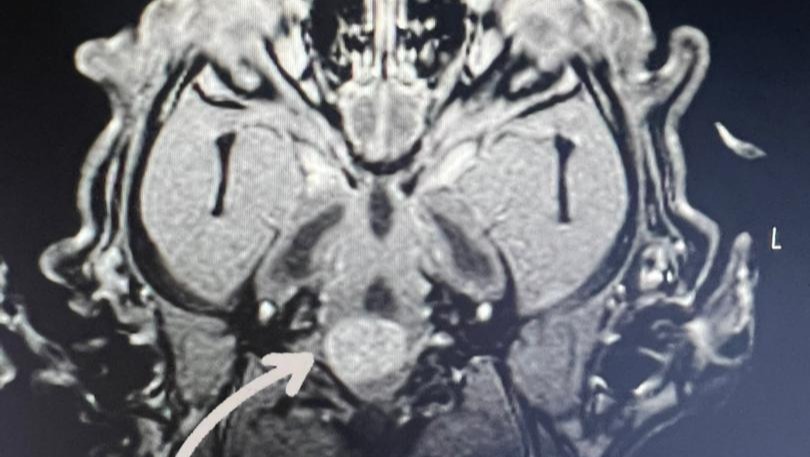

Dejaré anexadas fotos del presupuesto y de la resonancia magnética que le realizaron a Stitch en donde se observa el tumor (que está entre el cerebelo y la columna; una ubicación sumamente complicada de operar) y también se observa su tamaño (es como una pelota de Ping pong, es decir, muy grande). Eso le está causando obstrucción del líquido cefalorraquídeo y crea una hidrocefalia, la cual causa que Stitch no pueda caminar con normalidad, respirar, un síndrome vestibular y otras afecciones que poco a poco le costarán la vida.